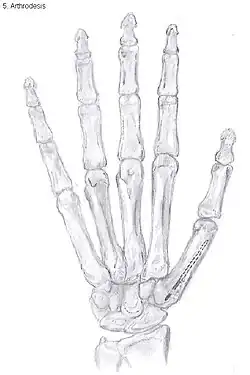

Arthrodesis

Arthrodesis of the TMC joint is a surgical procedure in which the trapezium bone and the metacarpal bone of the thumb are secured together. They are held together by K-wires or a plate and screws until the bone will heal.

Disadvantages include inability to flatten the hand.[27] Additionally, the stress on the CMC joint is now spread over the adjacent joints, those joints are more likely to develop osteoarthritis.[34]

Nevertheless, this procedure can be used in patients with stage II and III CMC OA as well as in young people with posttraumatic osteoarthritis.[27]